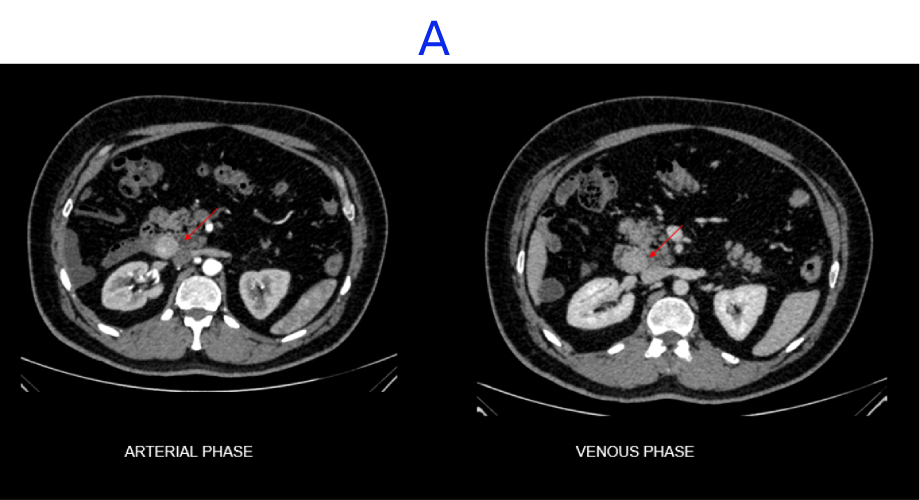

A. A well-defined, heterogeneously enhancing lesion seen in the D3 segment of the duodenum.

B. Few internal non-enhancing areas are seen in the superior aspect of the lesion.

C. A focal defect seen in the inferior aspect of the lesion, suggestive of ulceration.